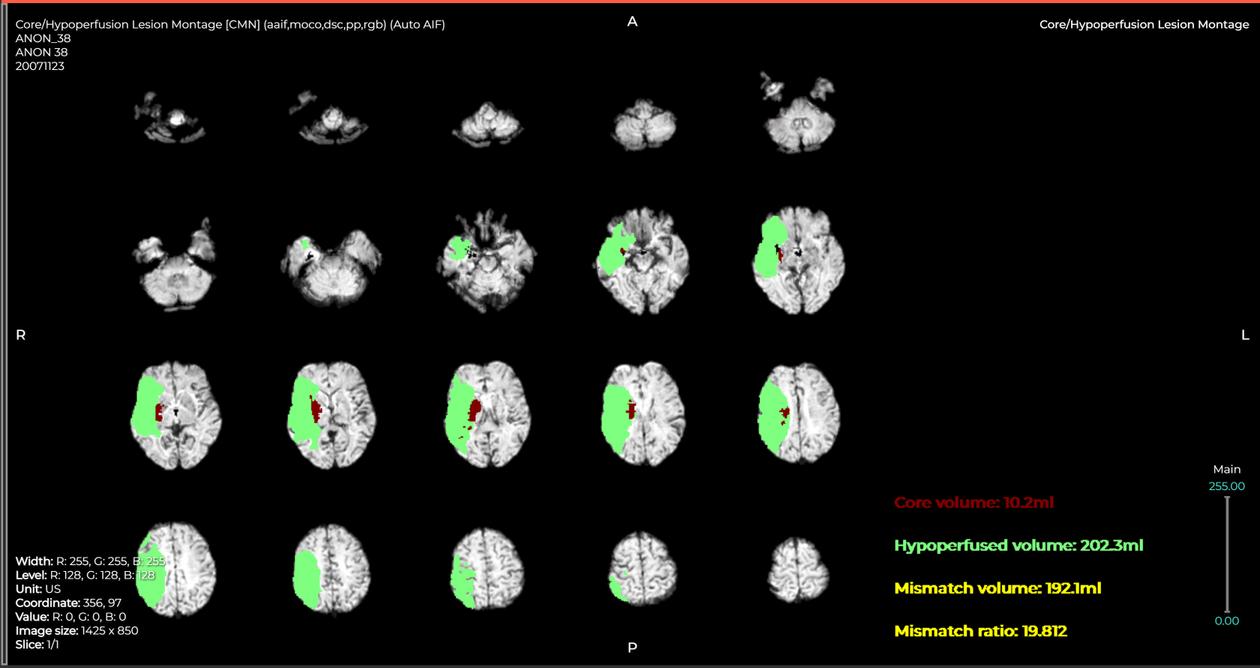

A l’hôpital de Garches (Hauts-de-Seine), c’est à la faveur de l’ouverture de l’unité neurovasculaire qu’un logiciel d’IA est utilisé depuis septembre 2021 pour « quantifier le volume de cerveau touché lors d’un accident vasculaire cérébral [AVC] ischémique [à la suite d’un caillot] », détaille la professeure en neuroradiologie Myriam Edjlali-Goujon : « Nous utilisons l’algorithme après l’IRM et avant la prise de décision humaine. Cette information identifie la zone du cerveau perdue et celle en pénombre, mise en hibernation, potentiellement “sauvable” si on agit vite. »

Habituellement, ce travail de volumétrie « long et fastidieux est fait manuellement, mais time is brain [“le temps, c’est du cerveau”] », explique-t-elle : « Après un an de vérification de reproductibilité des résultats, le logiciel apporte une vraie qualité de réponse. » L’avantage ? « Cela nous permet de fonctionner de façon fiable vingt-quatre heures sur vingt-quatre, sept jours sur sept. » Une approche algorithmique similaire appliquée à 111 000 patients au Royaume-Uni a permis de tripler (48 % contre 16 %) la part des personnes « récupérant sans handicap ou avec un handicap minime »après un AVC, a affirmé, dans un communiqué du 27 décembre 2022, le département de la santé et des affaires sociales britannique.